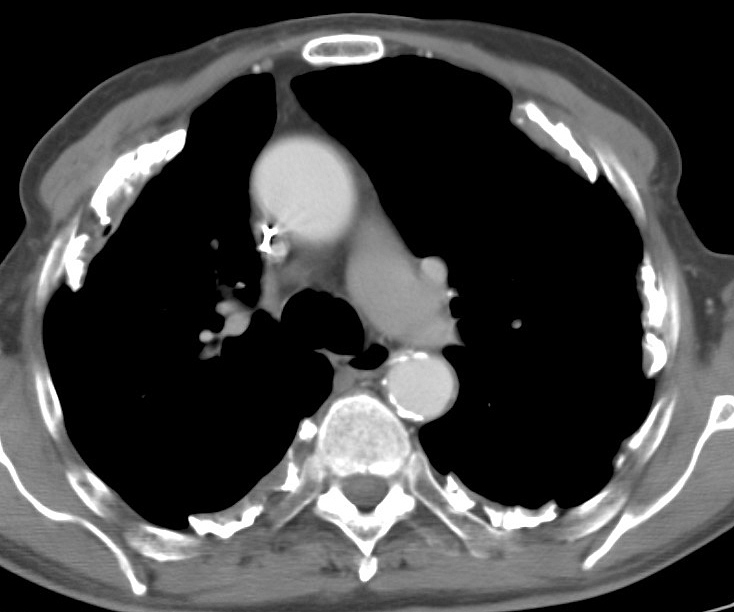

Asbestos 1 CT

Date: 06/02/2004